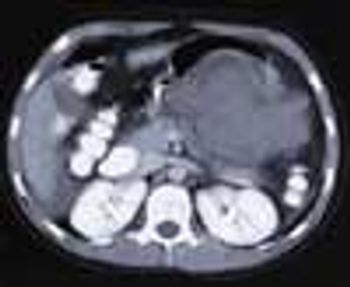

An HIV-positive 38-year-old man with a history of injection drug use presented to the emergency department with abdominal and back pain that worsened with motion. He denied fever and vomiting. During the past 2 months, the patient had been treated for a urinary tract infection (UTI) 4 times and evaluated for a renal calculus, which had been ruled out. He was currently receiving ciprofloxacin, ibuprofen, and HAART.